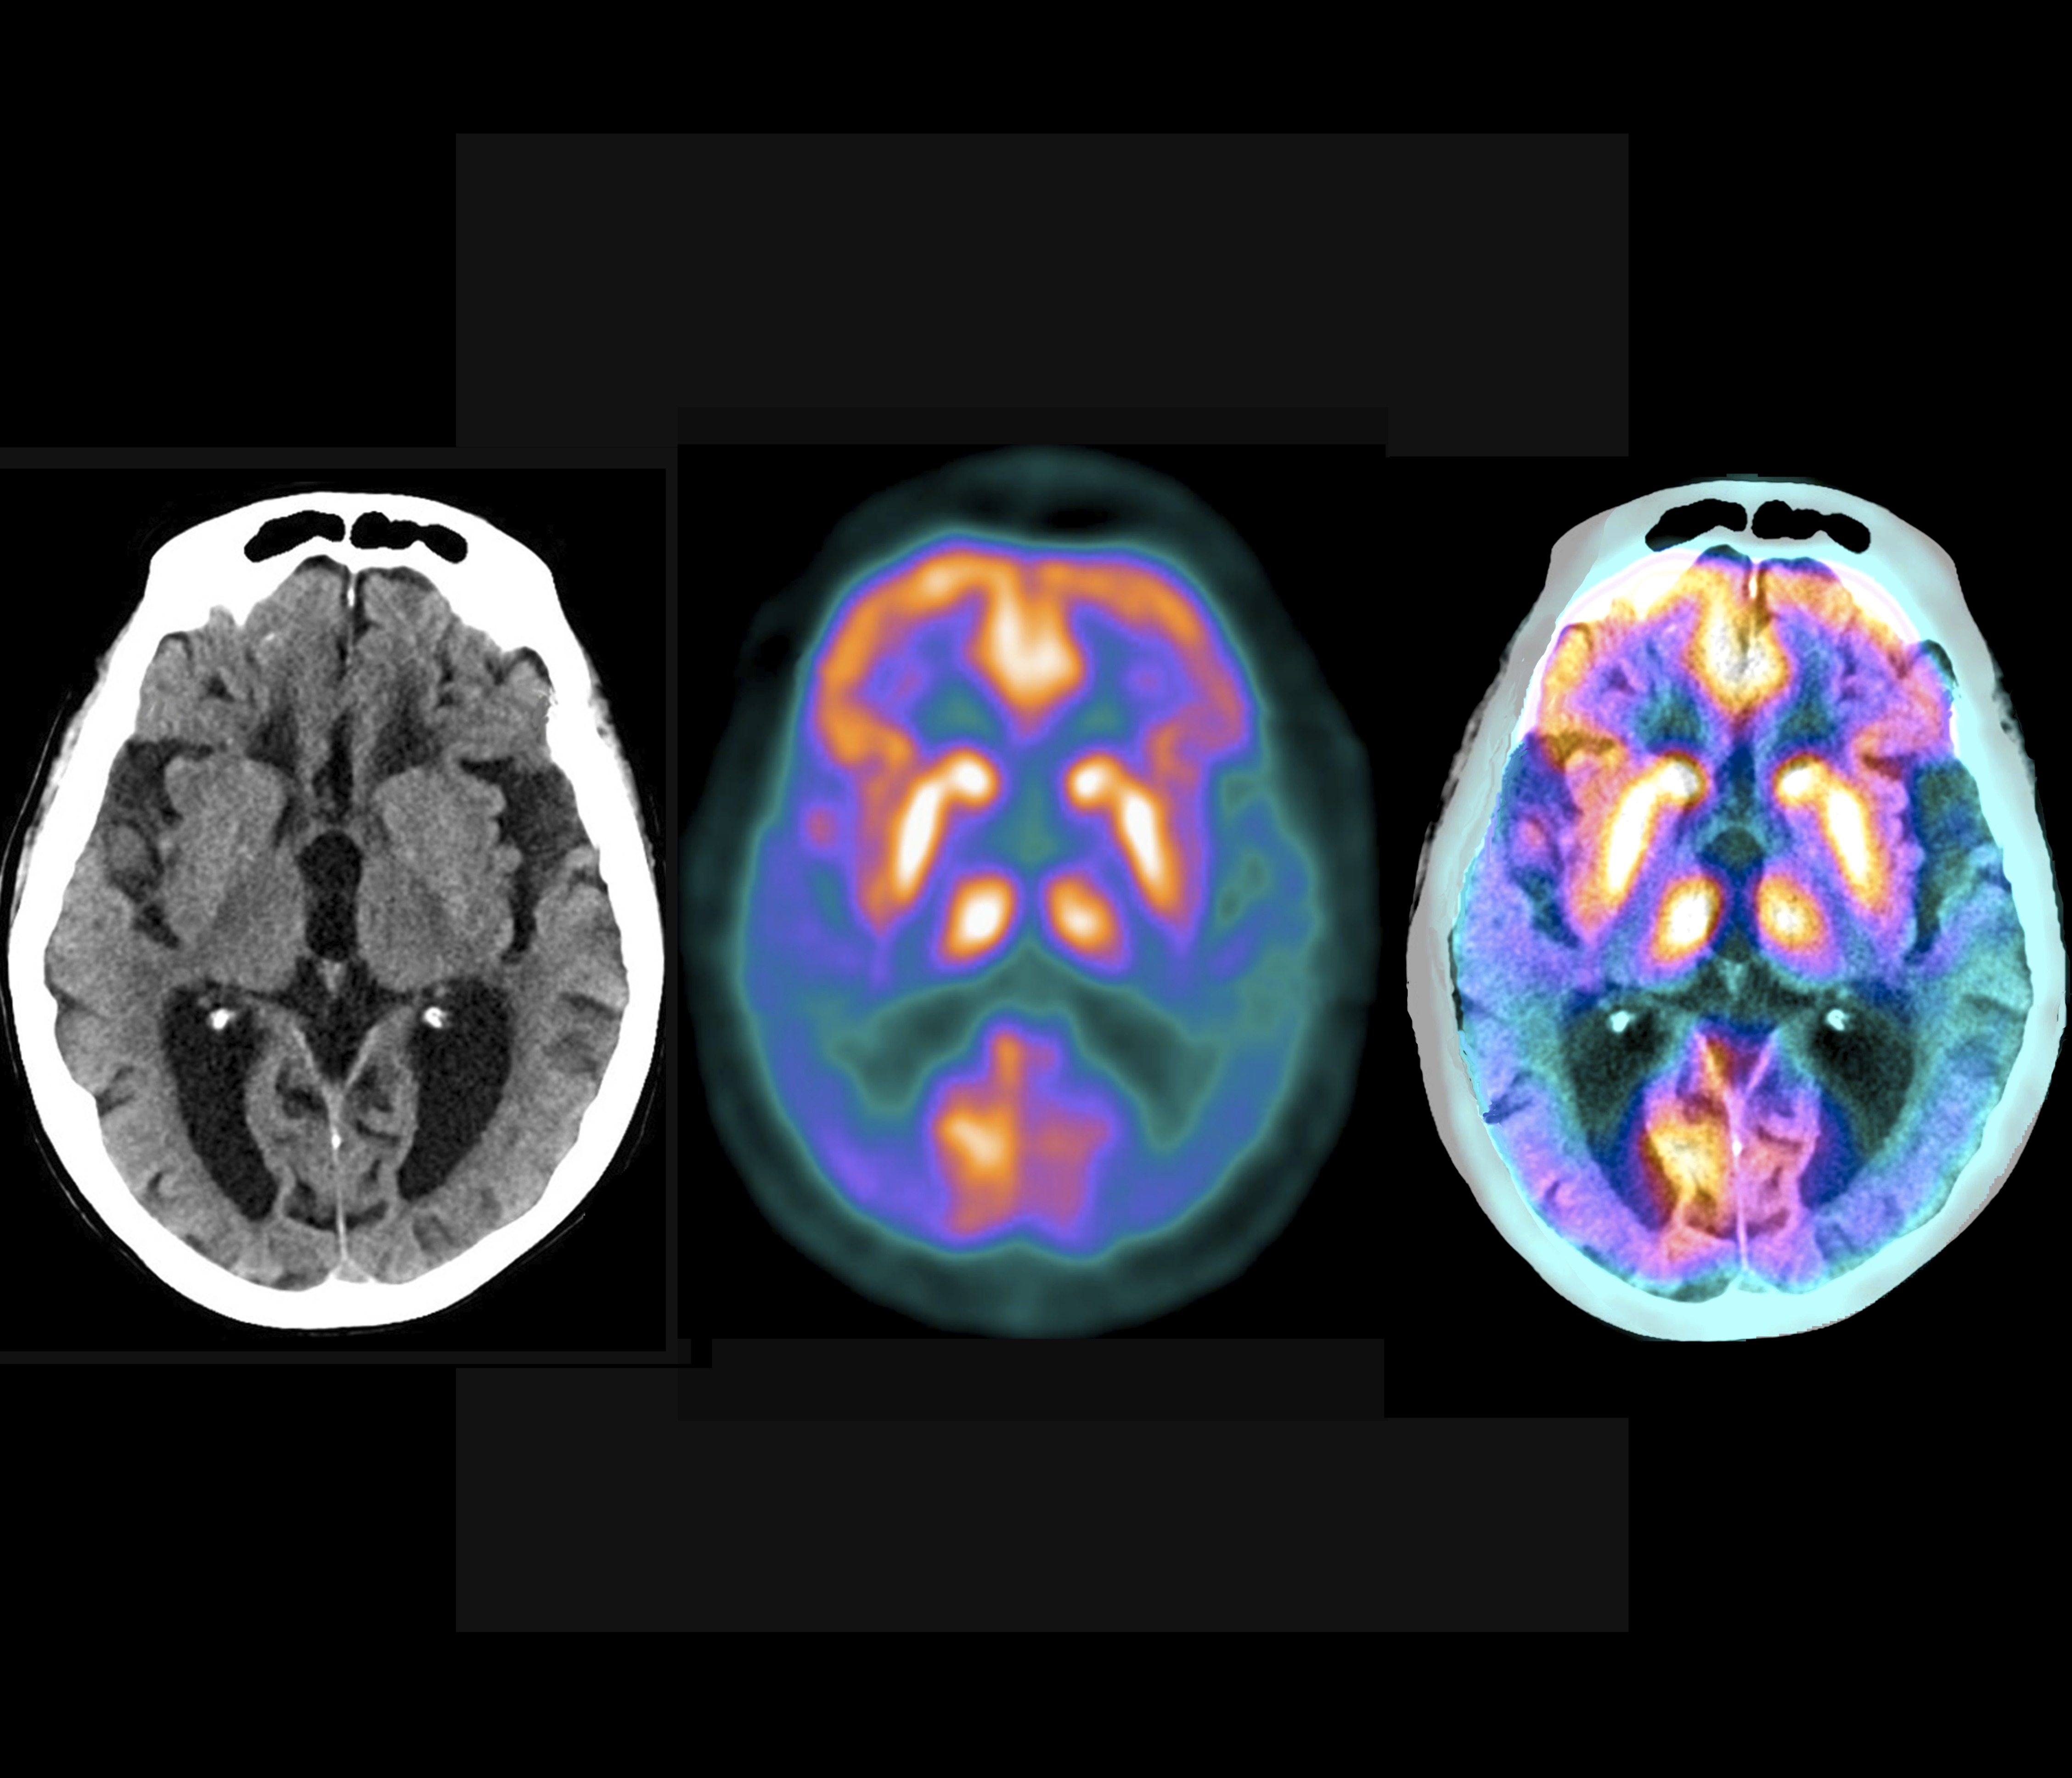

18F-kolin-PET/CT er en avbildningsteknikk som brukes for lokalisering av eventuelle hyperfungerende parathyreoideavev og parathyreoideaadenomer.

18F-kolin-PET/CT er en nyere avbildningsteknikk som brukes for lokalisering av eventuelle hyperfungerende parathyreoideavev/-adenomer. Teknikken har i økende grad blitt tatt i bruk på verdensbasis, og i Norge har bruken økt basert på egen erfaring (2). Ved Oslo Universitetssykehus har vi valgt å følge Språkrådet sin anbefaling om å benevne radiofarmakonet med norsk betegnelse, kolin. I startfasen ble undersøkelsen kun brukt i tilfeller hvor det var vanskelig å oppnå en sikker lokalisering ved konvensjonell avbildning. Metoden har vist seg å gi svært gode resultater, slik at konvensjonell nukleærmedisinsk metode ser ut til å fases ut gradvis (3).